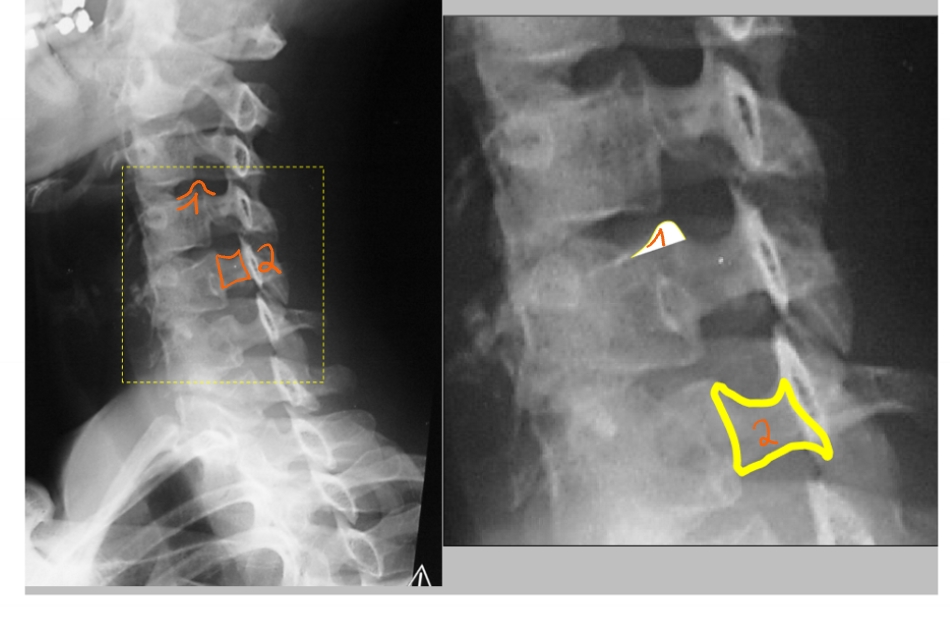

cervicale lordose

thoracale kyphose

lumbale lordose

annulus fibrosus

buitenste vezels

vangt de krachten op

nucleus pulposus

enige wat nog overblijft van de embryologische chorda

corpus T12

rib 12

zwevende rib

bovenrand van de arcus

processus spinosus

processus articularis inferior

pedikel

corpus L3

processus transversus (links)

ala van het sacrum (= de vleugels)

corpus S1

vetlijntje op de psoas-spier

rib 12

ribben niet perfect op elkaar want patiënt is een beetje gedraaid

corpus L3

pedikel

processus articularis superior

processus articularis inferior

processus spinosus

discus intervertebralis

spinale zenuw L2

foramen intervertebrale

sacrum

linker driekwart/ schuine opname

processus articularis superior

processus transversus

pedikel

isthmus = pars interarticularis

lamina

processus articularis inferior

CT-scan: sagittaal & parasagittal

(medio)sagittaal = door het midden

parasagittaal = een beetje naar links of naar rechts

conus medullaris

cauda equina (= paardenstaart)

nucleus pulposus

annulus fibrosus

→ MRI: T2-beeld

discus is donker in het midden = uitgedroogd

begint te verslijten → 1e stadium van degeneratief discuslijden